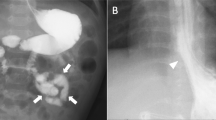

In view of the definite diagnosis of hypoproteinemia, the digestive, endocrine, and cardiac systems were next screened in detail. For the digestive system, a stool occult blood test was positive and the D-xylose absorption test was 0.9 g/5 h (normal > 1.2). Gastroduodenoscopy showed a snowflake appearance in the duodenum (Fig. 1a and b), a sign of lymphangiectasia. CT reconstruction of the small intestine showed that the descending duodenum wall was coarsely thickened and the small intestinal wall was sectionally thickened, enhanced, and locally narrowed (Fig. 1c and d). There was no obvious colonic abnormality.

a shows the snowflake appearance of the duodenum and b shows the granuloid changes in the gastric antral mucosa by electronic gastroscopy. Reconstructive CT of the small intestine in (c & d) demonstrate segmental thickening of the intestinal wall with local intestinal stenosis. Arrows highlight the indicated features